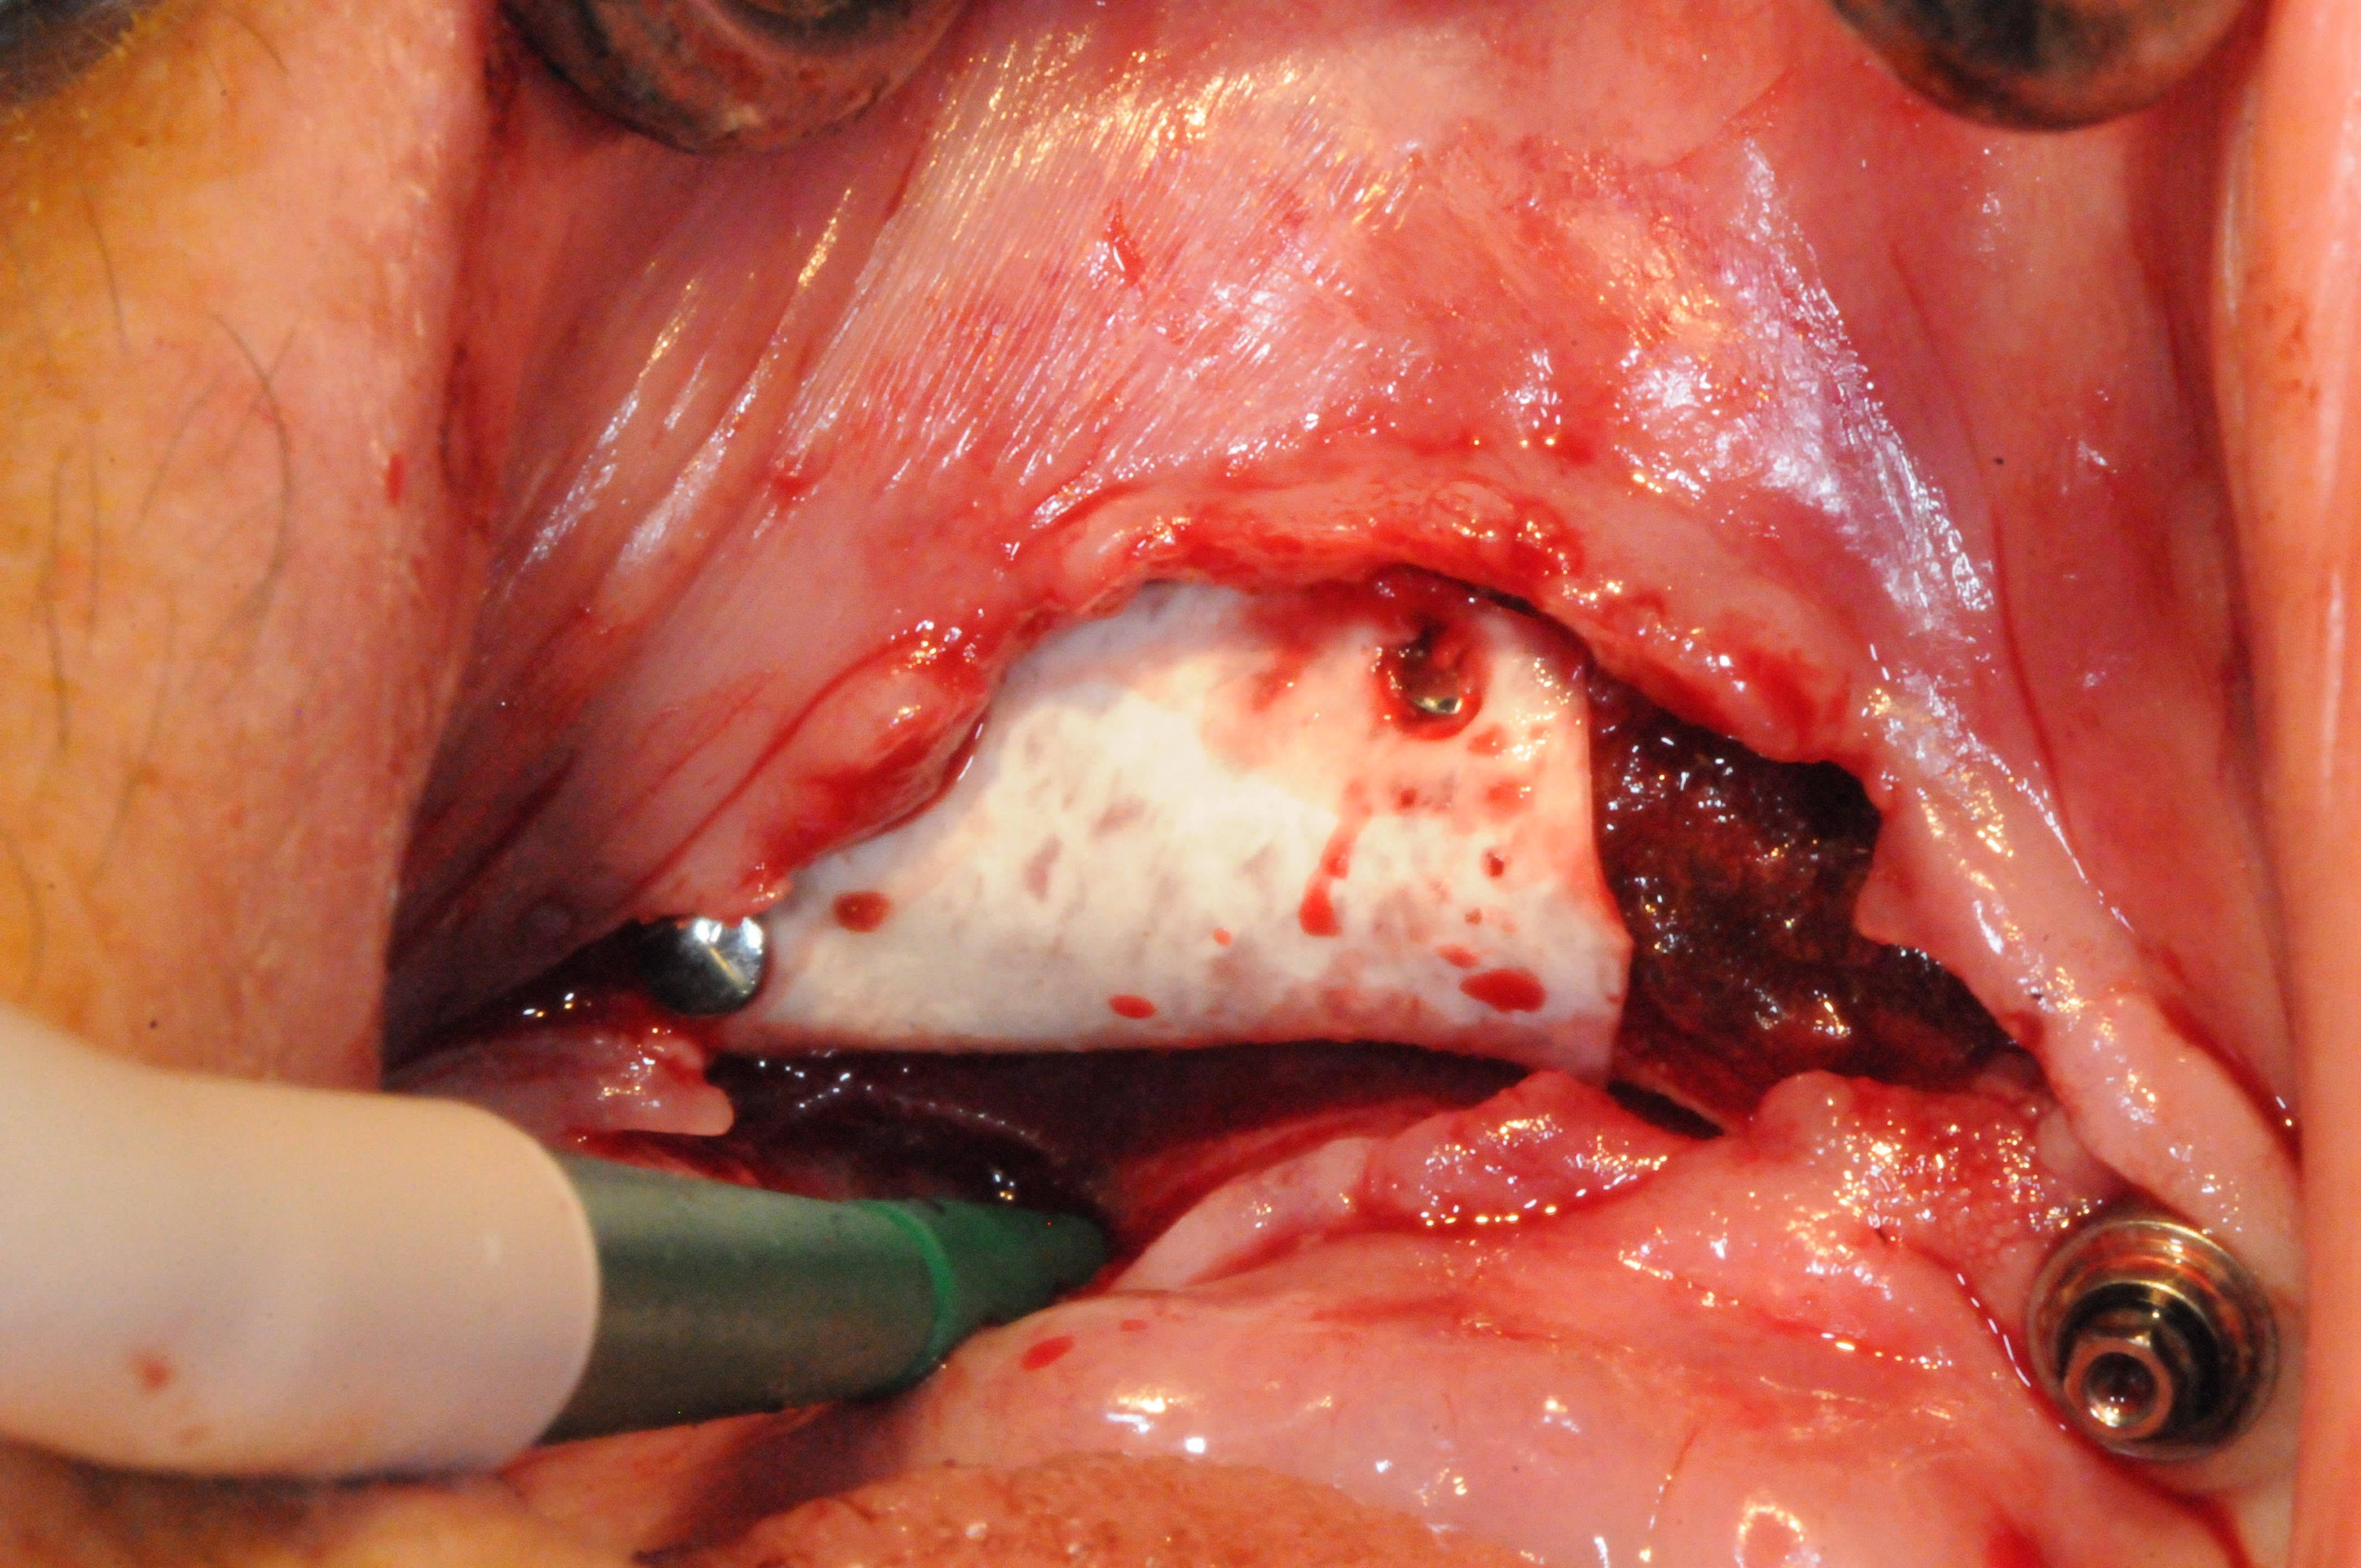

et bien la suite c'est ça .

et évidement, ça arrive quand c'est pas le moment.

Tu veux dire que désormais, avec la perte de deux implants contigus avulsés pour cause de péri-implantite, le all on four est transformé en all on two?

effectivement, c'est la chose la plus importante à gérer pour le moment.

je complète le cas;

82 ans

pose des implants par un praticien de Metz il y a10 ans. aucun problème particulier.

la prothèse venait d'être faite juste un peu avant le rachat du cabinet.

pratiquement aucune visites en 10 ans ...

la patiente est venue me consulter car elle souhaité la même chose au maxillaire. c'est là que j'ai découvert le pot aux roses il y a 3-4 semaines.

je lui ai dit que pour moi il était urgent de virer les implants et de prévoir une reconstitution osseuse au plus vite.

réponse de la patiente pas du tout motivé ( je peux le comprendre) ; après les grandes vacances, la communion du petit dernier, le voyage au Portugal, etc.... bref pas avant 5 mois...

elle a été prévenue du risque de casse.

au final, les vis ont cassées dans les piliers multi-unit vendredi dernier.

intervention pour retirer le kyste et curetage avec reconstruction osseuse par ROG ( bioos, membrane et tutti quanti..)

empreinte des piliers multi unit après avoir galéré pour retirer les vis cassées (d'où le coût plus élevé que si ça avait été fait avant)

repositionnement de la prothèse sur le modèle en plâtre pour retrouver la DV

réalisation d'un autre complet haut et bas avec DV et courbe occlusale convenable.

la suite dans quelques mois quand il y aura de l'os...